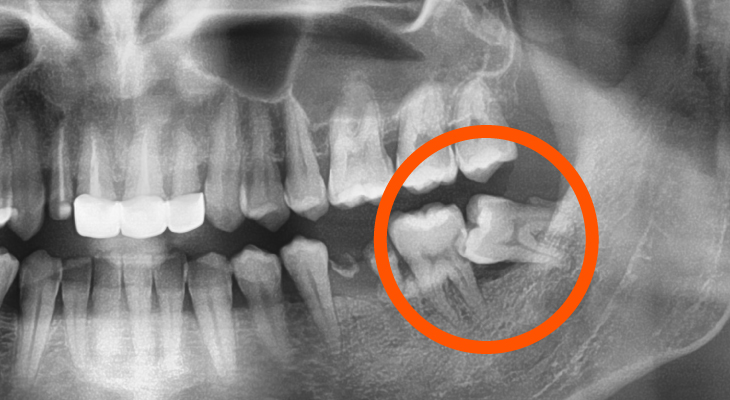

侵犯鄰牙

通常患者不會知道,需由醫生以X光診斷。

原因為萌發的空間不足,而會倒在第二大臼齒上,因而造成清潔不易,甚至是牙齒部分吸收,造成不舒適或牙痛。

阻生齒

不一定有感覺,這一種類型的牙齒,通常埋在齒槽骨的裡面,如果會痛,或是診斷會有病原發生的時候,就需拔除。

這兩顆牙齒對患者都未造成不適,但卻造成了嚴重的牙周病兩顆牙齒間的骨頭有明顯的破壞。

牙齒周圍的骨頭就像是牙齒的地基,骨頭流失後的牙齒就會開始鬆動,甚至有時牙周病已經非常嚴重到第二大臼齒也難逃被拔除的命運。